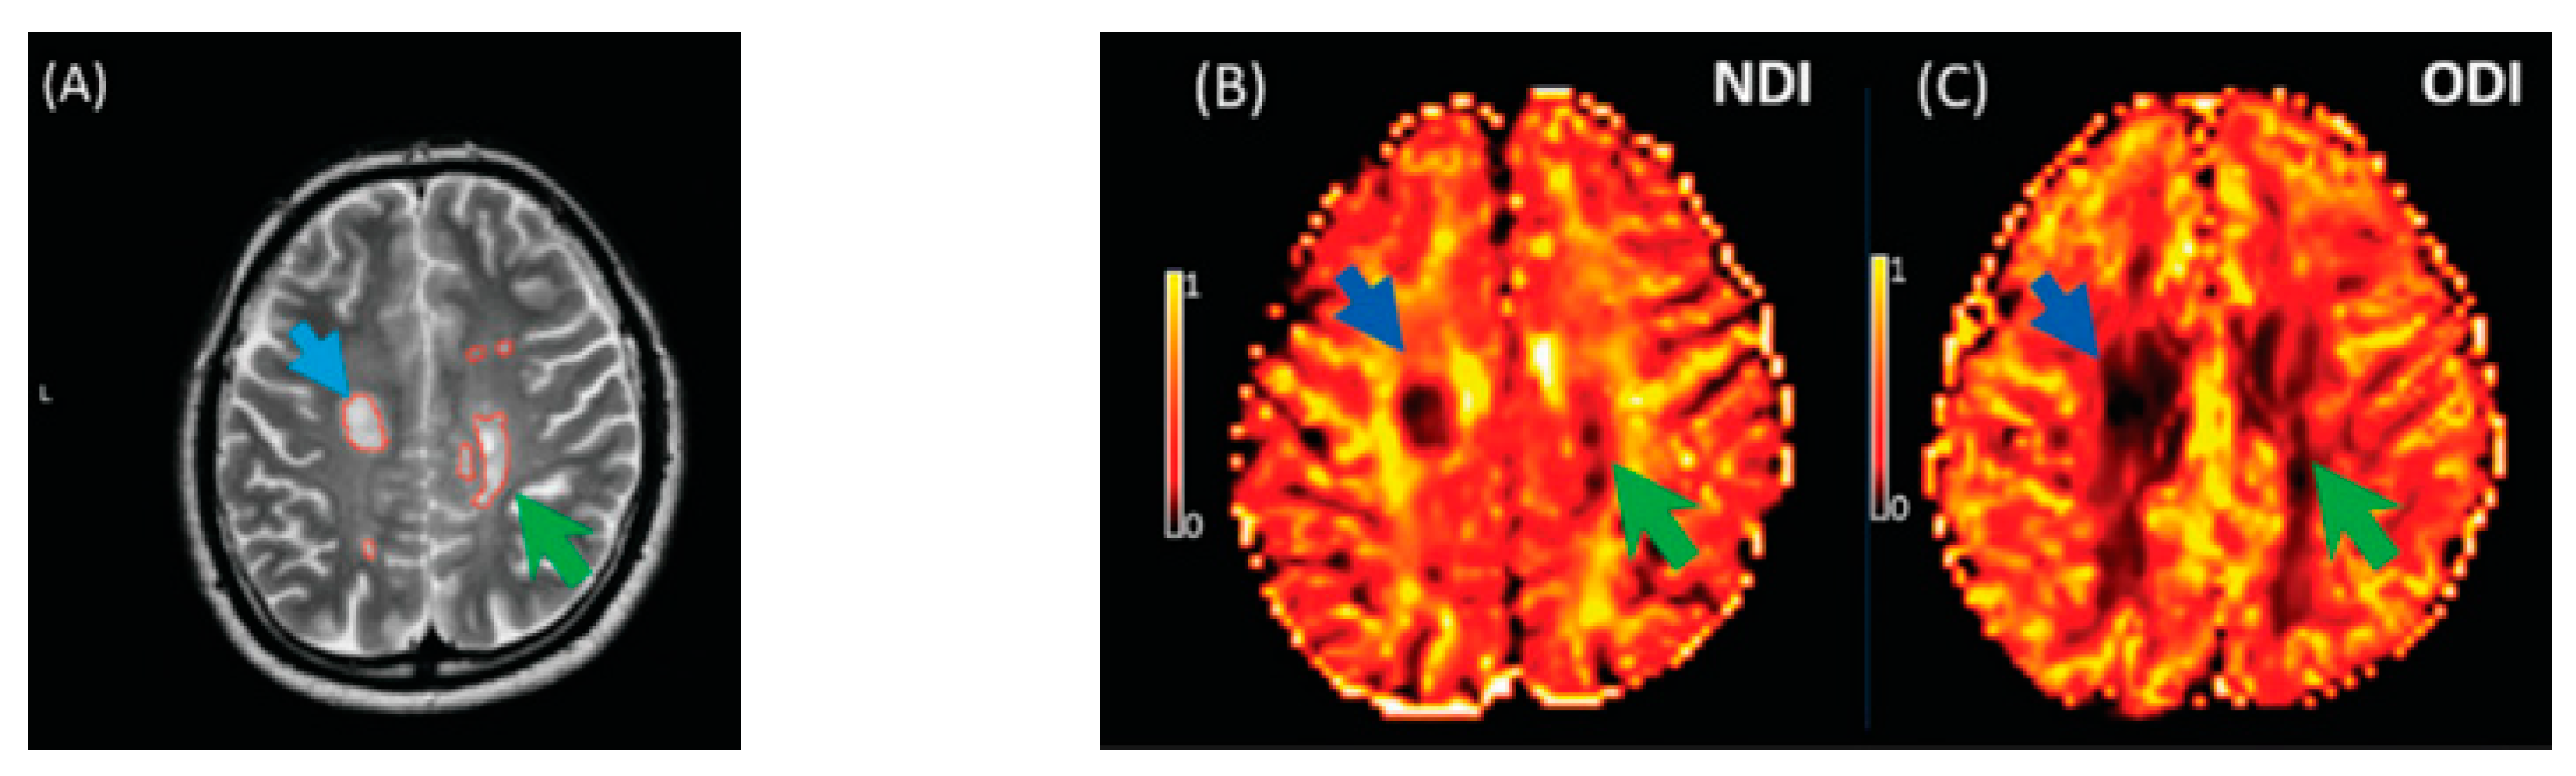

The key finding of this meta-analysis of ROI data concerned that the NDI was reduced in MS lesions and NAWM compared to healthy controls (Figure 8). This significant reduction of the NDI corresponds to reduced intracellular signal fraction and may reflect underlying damage or loss of neurites. Previous work has shown that this reduction is accompanied by higher MD and lower FA [24], and the higher ODI suggests demyelination, axonal loss, and less coherence in the fibre orientation (bending or fanning axons) [23]. This meta-analysis demonstrates a significant reduction of intracellular signal fraction in the NAWM of MS subjects compared with the WM of controls, suggesting early axonal pathology outside demyelination in WM lesions [30,31,32,33]. This consistent reduction among all studies proves that the NDI (through its sensitivity to the intra-axonal compartment) may quantify and differentiate microstructural changes in WM MS lesions, in the NAWM of MS, and in healthy WM. This suggests a loss of axonal density in WM lesions and NAWM in MS compared with healthy controls, which is consistent with previous DTI studies [10,34] reporting altered water diffusion in NAWM and WM MS lesions compared with controlled subjects. Interestingly, the reduction of the NDI in WM lesions and NAWM is in line with previous pathological studies showing axonal loss within WM lesions and a lesser degree in NAWM [17,33,34,35]. This consistent reduction of the NDI reported in this meta-analysis may further assist researchers in relying on NODDI metrics in biophysically understanding the axonal loss/damage in WM lesions and NAWM.

Figure 8.

Illustrates NODDI metrics in a single slice of one MS subject. The MS lesion in the major white matter tracts (blue arrow) and periventricular lesion (green arrow) are marked in a structural MRI image (A), NDI map (B), and ODI map (C). Both the NDI and ODI are decreased in the MS lesion [20].